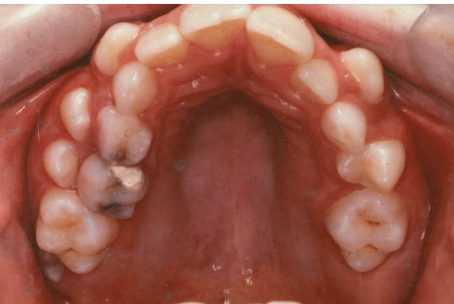

what age is this patient

6 or 7

which other permanent teeth should be present at this time

first permanent molars (6s)

what is the name given to the space between the upper central incisors

midline diastema

what has caused this in this particular case

low frenal attachment

what is the likely cause of the general appearacnnce of the lower central incisors

fluorosis

how is fluorosis likely to have arisen

excessive ingestion of fluoride during development of the teeth

what other permanent teeth are likely to affected by fluorosis

upper centrals

lateral incisors

canines

first premolars

second premolars

first molars

give 3 tx options for lower central incisors

microabrasion

composite restoration

strip crowns

which primary teeth are still present

55

54

53

63

then adults 16, 12, 11, 21, 22, 25, 26